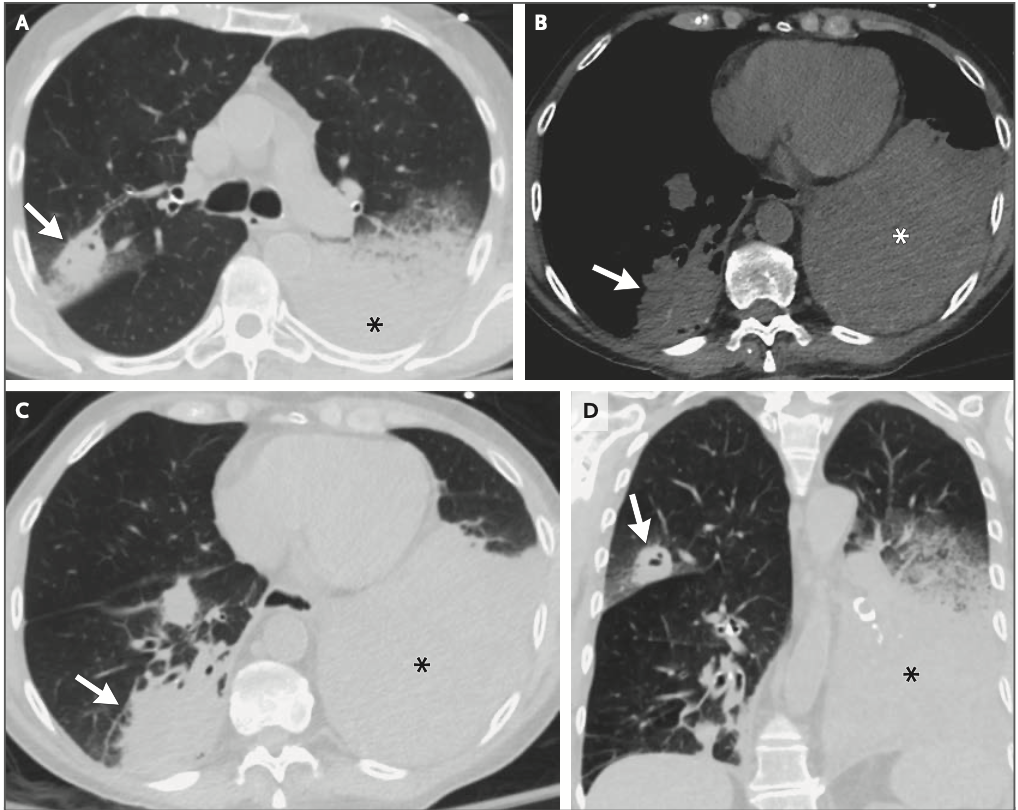

右上葉に空洞影と左下葉に巨大な腫瘤影を認めた